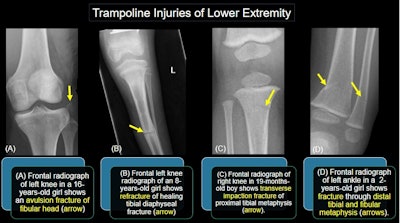

To illustrate the spectrum of injuries, Gupta presented a series of images with positive findings. The range of injuries includes those affecting the head and neck, chest, abdomen, and musculoskeletal system, including neurovascular injuries. While limb fractures are the most observed injuries, spinal and facial bone injuries as well as nonskeletal soft tissue injuries are also seen, she said.

Image courtesy of the ARRS.

Unique trampoline-related injuries include proximal tibial fractures, sternal injuries, vertebral artery dissection and atlanto-axial subluxation, Gupta noted.